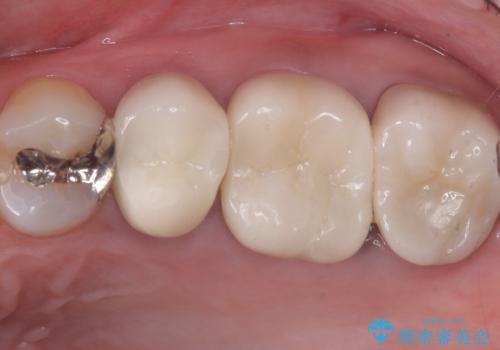

【セラミッククラウン】土台と被せものがズレている気がする

過去に入れた被せものと土台の歯との適合が悪く、隙間が出来ておりそこに汚れが溜まりやすい状態になっていました。セラミッククラウンでのやり替えとなりました。

唇側マージン不適なこと説明し、審美性・適合性に優れたセラミッククラウン(スタンダード)でのやり替えとなりました。

治療途中、一度仮歯に置き換えを行っています。